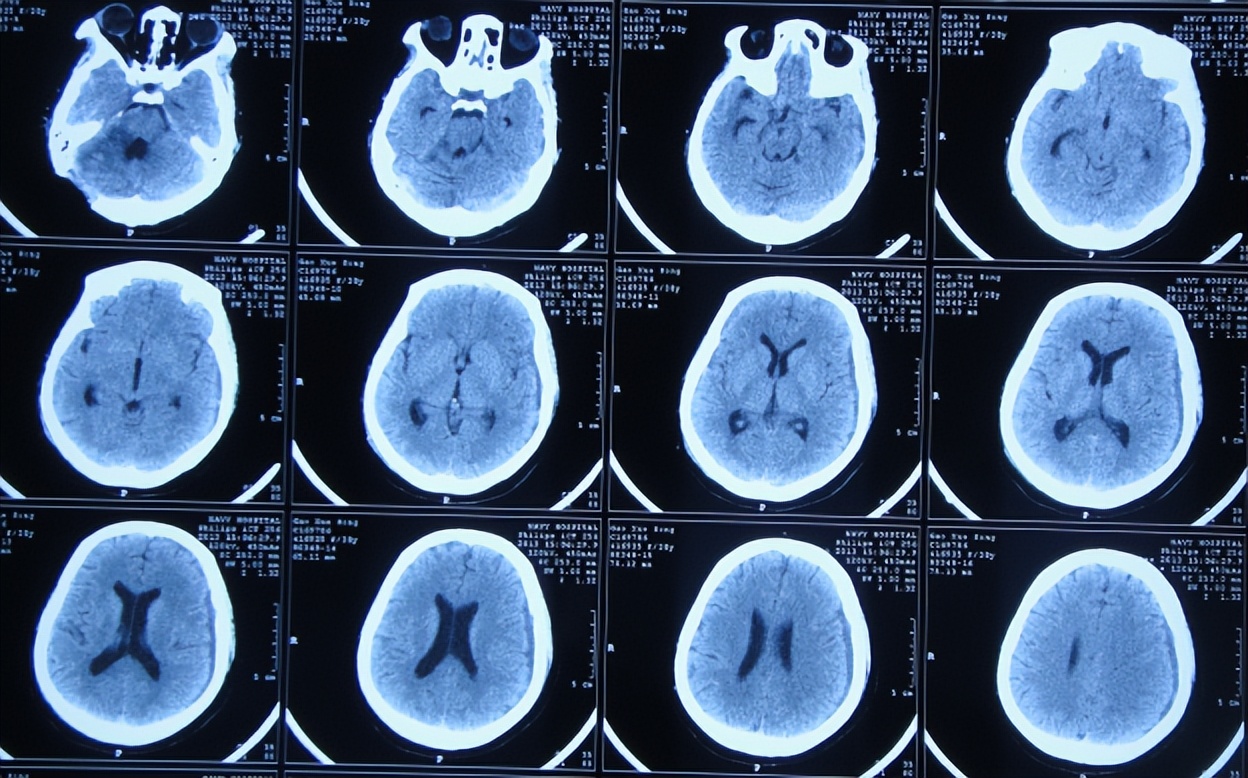

患者高老师是一名高中历史教师,右耳听力减退已10余年未给予特殊治疗,但2013年11月因出现病情严重的头疼头晕症状,到当地的山西省静乐县某医院,查头颅CT(图-1)后颅内肿瘤占位,需要手术。

图-1:2013年11月6日头颅CT

听神经瘤切除术后7天即2013年11月21日,查头颅CT示仍有血肿(图-3),出现发热,最高体温体温38.3 ℃左右,给予腰穿检查脑脊液后认为有感染,给予腰大池引流术及鞘内注射万古霉素。

图-3:2013年11月21日头颅CT

腰大池引流术后12天即2013年12月3日(听神经瘤切除术后19天),期间仍反复发热,查头颅CT示一侧脑室扩张大,硬膜下水肿(图-6),担心加重颅内感染,改行腰穿治疗。

图-6:2013年12月3日头颅CT

听神经瘤切除术后28天即2013年12月12日,查头颅CT示仍有一侧脑室扩张(图-7)。

图-7:2013年12月12日头颅CT

听神经瘤切除术后42天即2013年12月26日,查头颅CT(图-8)后持续交替给予腰大池引流、腰穿治疗并联合鞘内注射。

图-8:2013年12月26日头颅CT